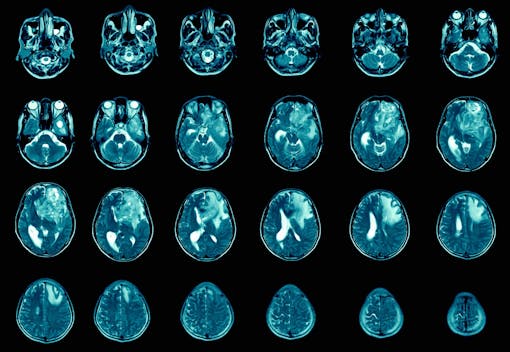

Glioblastoma is a devastating brain cancer that grows fast and invades surrounding brain tissues. It is the most prevalent brain tumor in adults, affecting roughly 12,000 Americans every year. Survival after diagnosis generally ranges from 15 months to 18 months. The five-year survival rate of patients with glioblastoma is 5%. Because of this grim prognosis, clinicians agree there is a desperate need for a cure.

In patients with glioblastoma, cancerous astrocytes form a rapidly growing tumor. The current treatment for glioblastoma involves surgery followed by radiation and chemotherapy. Even with treatment, the tumor regrows, and 95% of patients die within five years of their initial diagnosis.